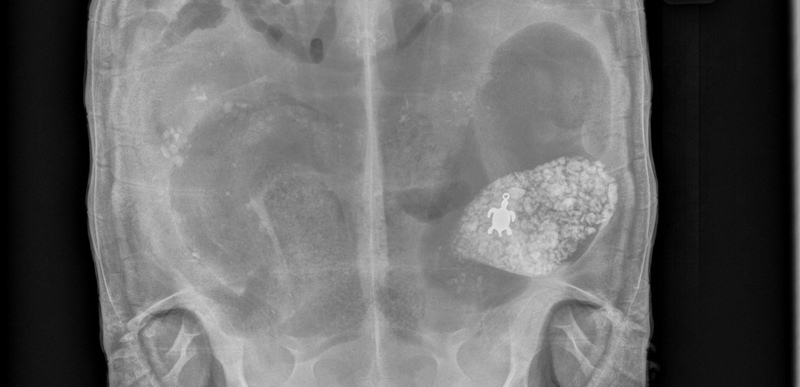

This Monday, Oct. 27, 2014 photo provided by Dr. Don Harris of the Avian & Exotic Animal Medical Center in Miami shows an X-ray of a 15-pound male African spurred tortoise named Lola who had swallowed a turtle pendant. (AP Photo/Dr. Don Harris)

MIAMI — The source of a sick tortoise’s discomfort became clear after a south Florida veterinarian took an X-ray: The animal had swallowed a turtle pendant.

After an X-ray, Harris spotted the small, turtle-shaped object inside his patient.